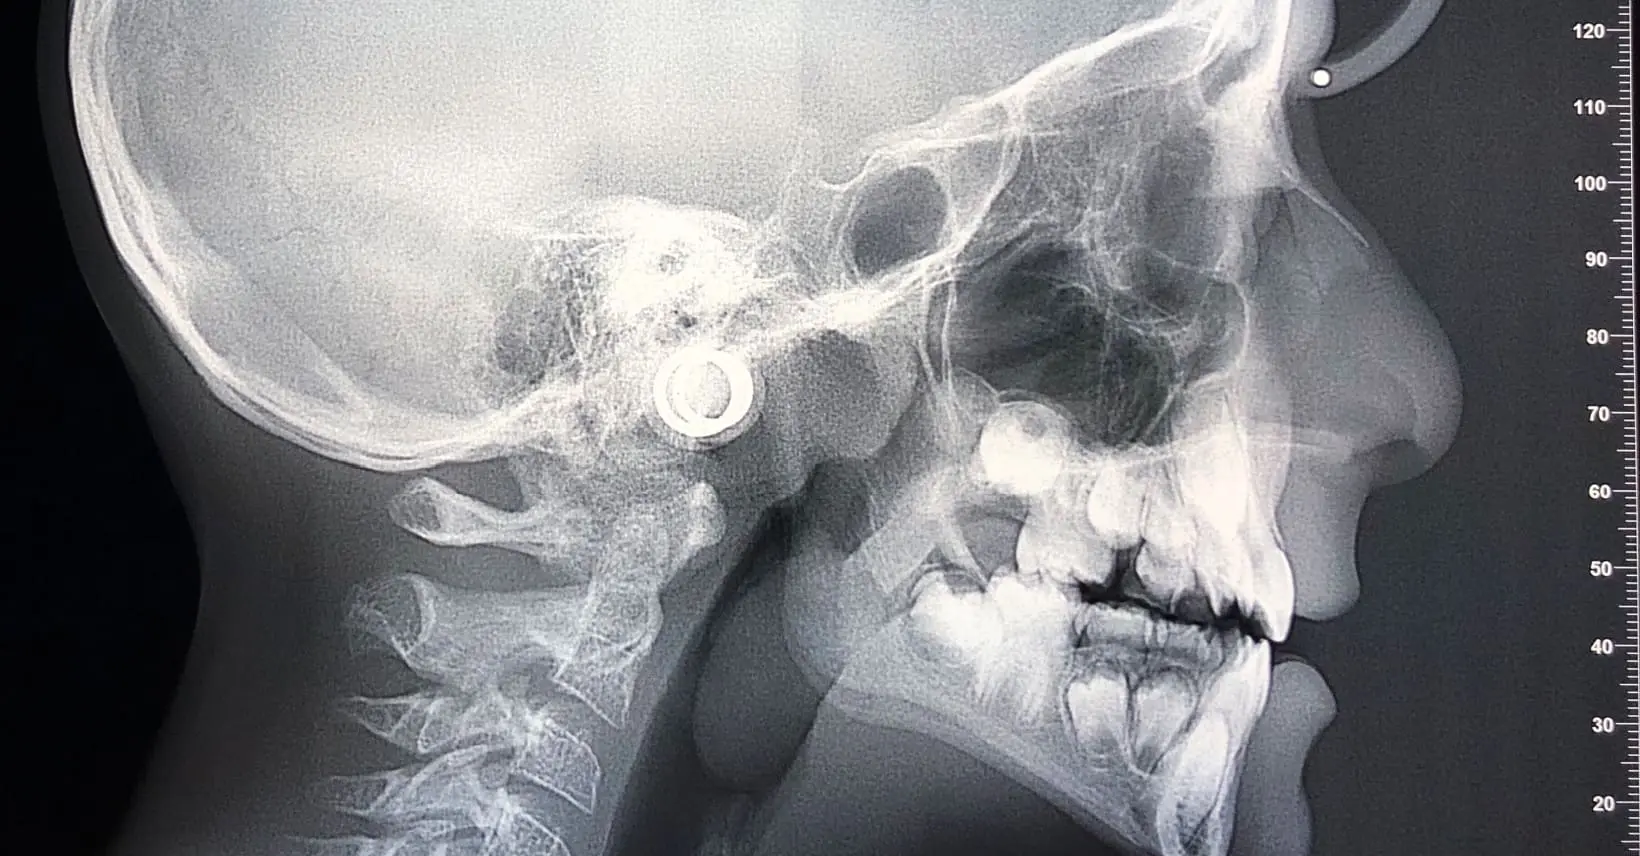

The numerical values are interesting, Would have been nice to see some pre and post cephs to visually see the treatment effects.